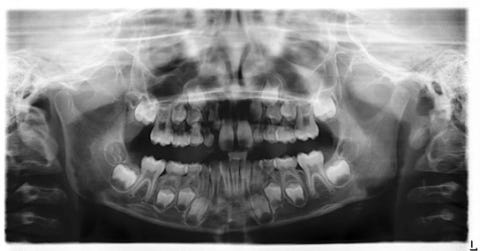

Een Tandcorrectie voor kinderen is belangrijk om scheve tanden of een verkeerde beet vroegtijdig te corrigeren. De ideale leeftijd ligt tussen 9 en 13 jaar, wanneer het gebit zich nog ontwikkelt.

Orthodontist clinics zijn gespecialiseerde centra die zich richten op het corrigeren van tanden en kaken. Ze gebruiken moderne technologie zoals 3D-scans, digitale afdrukken en op maat gemaakte beugels.